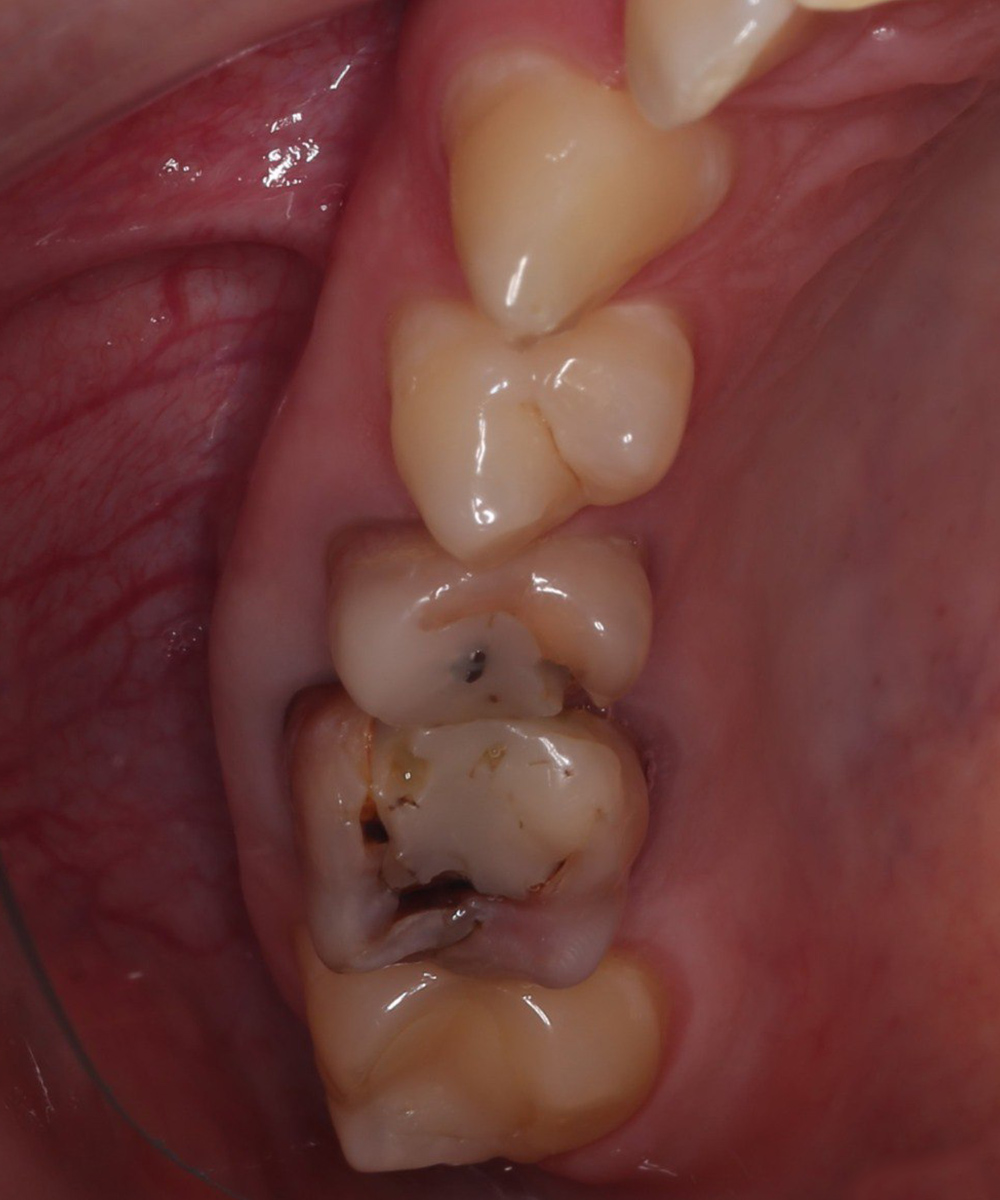

Замена сколовшейся пломбы на жевательном зубе циркониевой коронкой